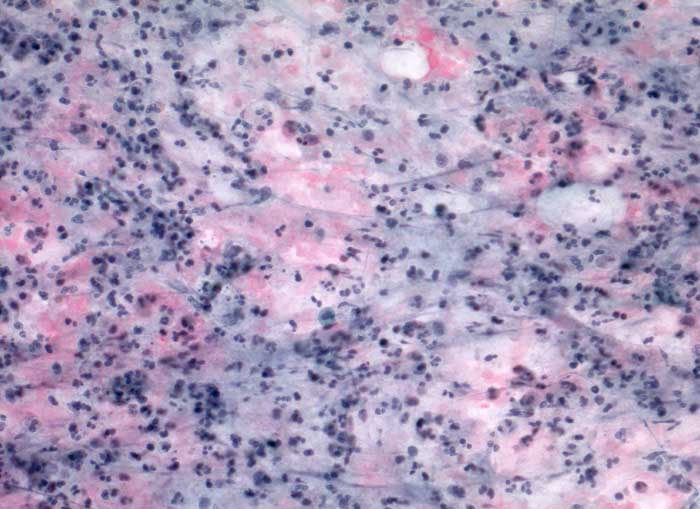

akute Sialadenitis

Parotis

Feinnadelpunktion Parotis: Im Hintergrund amorphes eiweissartiges Material. Massenhaft neutrophile Granulozyten und Makrophagen.

Akute Entzündung der Speicheldrüse DD: maligner Tumor

Keine histologische Untersuchung notwendig

Zytologie

200